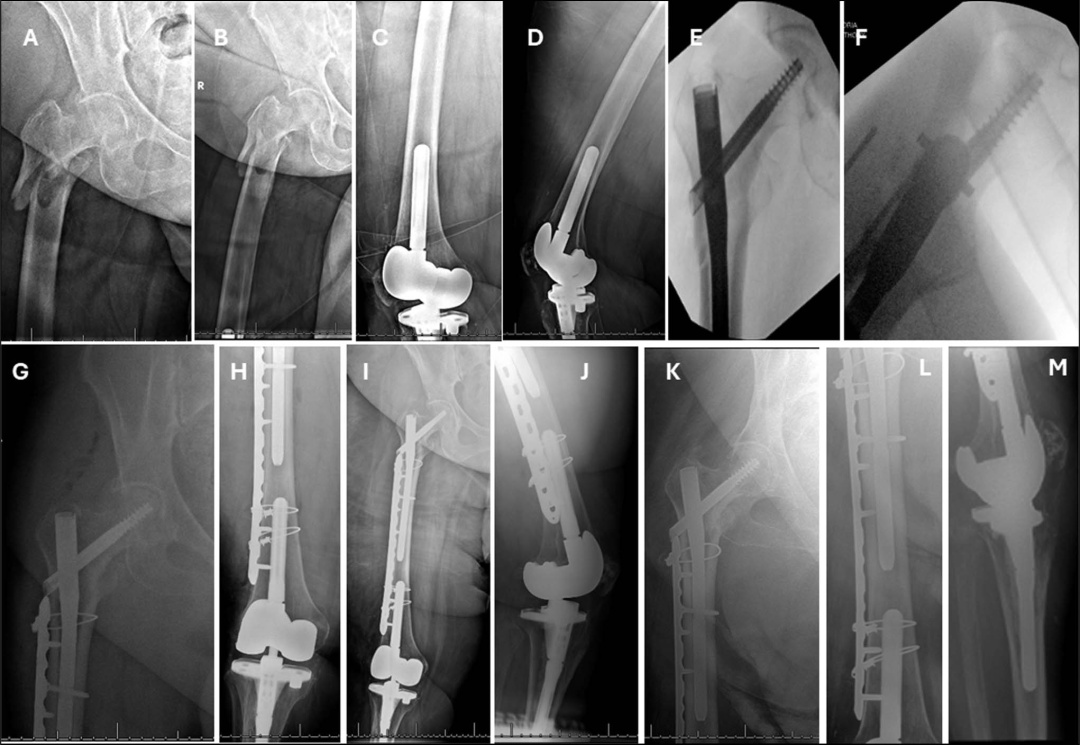

在任何粗隆间骨折类型中,中长度钉都可以作为短钉的替代品。绝对指征:低转子间骨折,延伸超过3cm远端至小转子底部存在远端柄植入物,如柄膝关节置换术(图)。

存在无法移除或不打算移除的远端股钢板(图)。

考虑到远端骨折延伸,使用短钉是不合适的,而由于远端髓内植入物的存在,不能使用长钉。

外侧壁骨折的存在是骨折内翻塌陷的潜在危险因素,特别是对于股骨髓腔较大的患者,在这些骨折中,较长的钉可能是首选(图)。